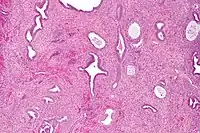

Micrograph of an endometrial polyp. H&E stain.

Myometrium (smooth muscle cells) versus endometrial stroma (more cellular) versus endometrial polyp stroma (more collagenous). H&E stain

Endometrial polyps can be solitary or occur with others.[11] They are round or oval and measure between a few millimeters and several centimeters in diameter.[7][11] They are usually the same red/brown color of the surrounding endometrium although large ones can appear to be a darker red.[7] The polyps consist of dense, fibrous tissue (stroma), blood vessels and glandlike spaces lined with endometrial epithelium.[7] If they are pedunculated, they are attached by a thin stalk (pedicle). If they are sessile, they are connected by a flat base to the uterine wall.[11] Pedunculated polyps are more common than sessile ones.[4]